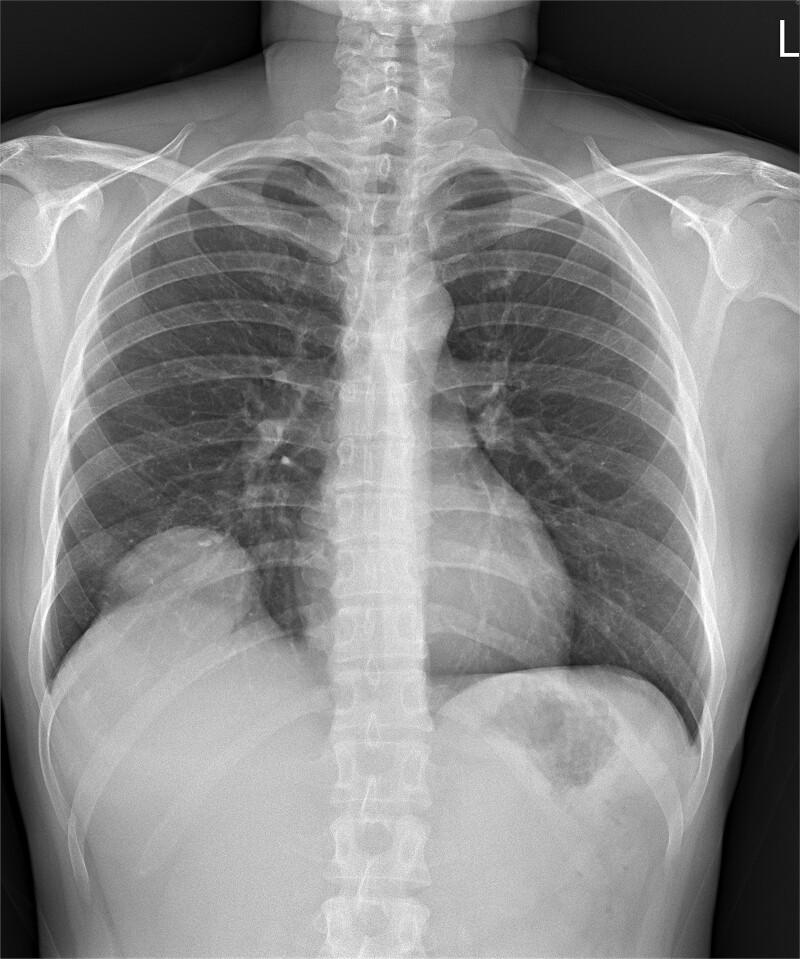

Hepatic sarcomatoid cholangiocarcinoma is a rare, accounting for <1% of cases and aggressive malignant neoplasm. This report presents a case of a 35-year-old female patient who presented with right shoulder pain, general weakness, anorexia, and weight loss. Imaging studies revealed a hepatic mass in segment S8, with invasion into the diaphragm and right lower lobe of the lung. The patient underwent surgical resection, and the pathological diagnosis confirmed hepatic sarcomatoid cholangiocarcinoma. This case report discusses the clinical presentation, diagnosis, and treatment of this rare malignancy, emphasizing the importance of early diagnosis and aggressive management.

肝肉瘤样胆管癌是一种罕见的侵袭性恶性肿瘤,占病例的不到1%。本报告介绍了一名35岁女性患者的病例,该患者出现右肩疼痛、全身乏力、厌食和体重减轻。影像学检查显示肝S8段有一肿块,侵犯膈肌和右肺下叶。患者接受了手术切除,病理诊断证实为肝肉瘤样胆管癌。本病例报告讨论了这种罕见恶性肿瘤的临床表现、诊断和治疗,强调了早期诊断和积极治疗的重要性。